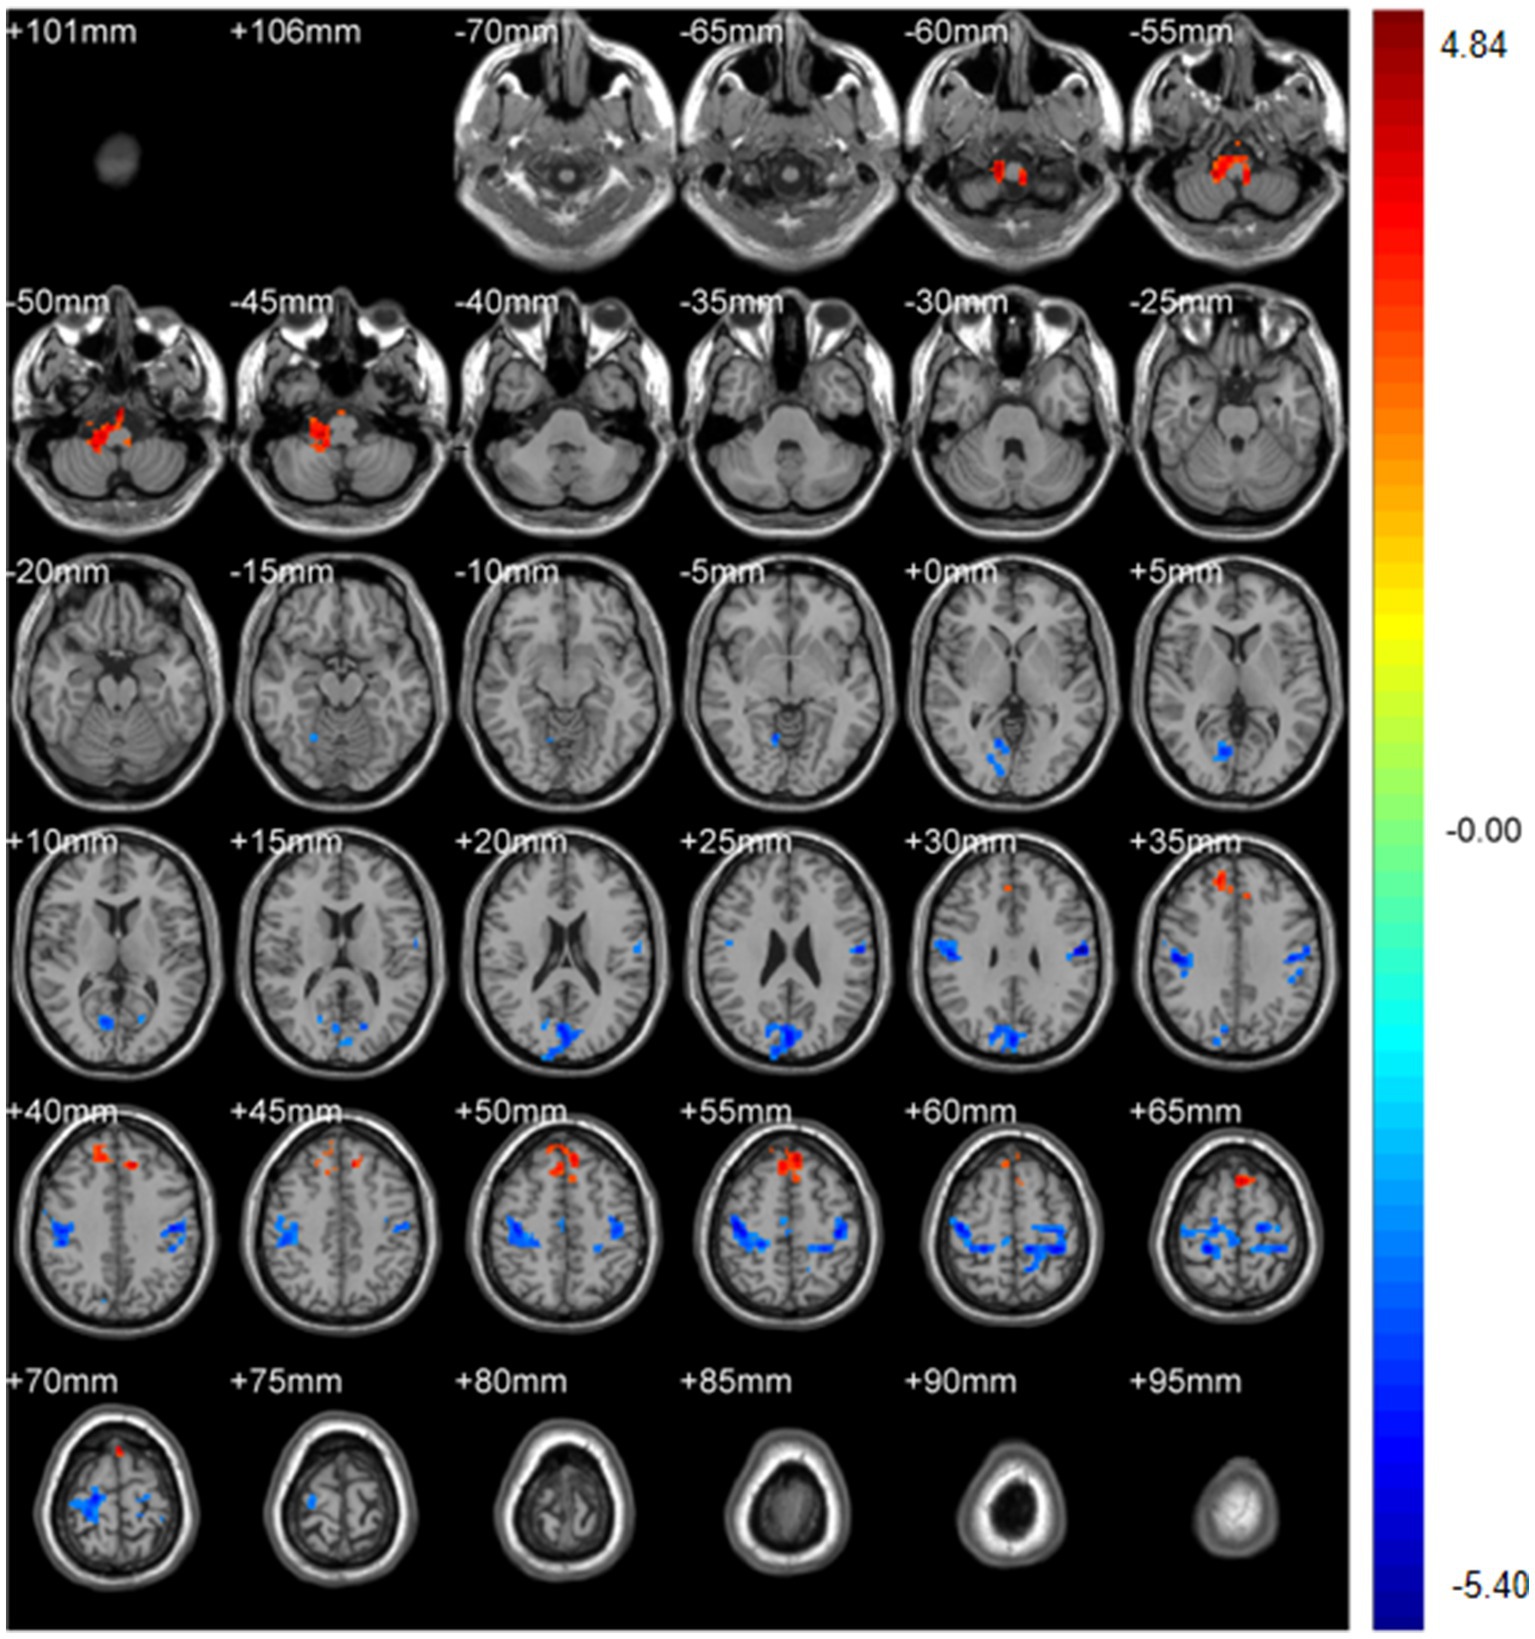

ABSTRACT Background: Spinal diseases related pain represents a critical clinical issue that demands urgent resolution. Current treatment and assessment strategies predominantly focus on peripheral mechanisms. The application of functional magnetic resonance imaging (fMRI) offers a promising approach to identifying potential central targets for intervention. Methods: We retrospectively included 31 patients with spinal diseases related pain and 32 controls with non-spinal, orthopedic complaints (no chronic neurological or psychiatric disorders). All participants underwent resting-state brain fMRI (eyes closed, awake). We quantified amplitude of low-frequency fluctuations (ALFF) with mean normalization (mALFF) and z-transformation (zALFF), regional homogeneity (ReHo; 27-voxel neighborhood), seed-based functional connectivity (FC; pre/postcentral seeds), and degree centrality (DC; binary and weighted). Between group tests used voxel-wise two-sample t_tests with Gaussian Random Field (GRF) correction. Results: Patient group was associated with increased m/zALFF in right cerebellar lobule IX and right Superior Frontal Gyrus, medial part , and lower activity in bilateral postcentral gyri and the Cuneus. , decreased m/zALFF in bilateral postcentral gyri. ReHo analysis confirmed reduced local synchrony in postcentral regions , spatially overlapping with ALFF findings. FC analyses revealed enhanced cerebellar-thalamic connectivity (Crus1/2, thalamus) but reduced connectivity in sensorimotor and higher-order cortical networks. DC showed hyperconnectivity in left cerebellar Crus I with reduced Superior Frontal Orbital (Frontal_Sup_Orb). All findings survived GRF correction at the pre_specified thresholds. Conclusions: Resting-state brain fMRI indicates a cerebello-thalamo-cortical alteration pattern in spinal diseases related pain featuring cerebellar involvement, prefrontal subspecialization, and multilevel sensorimotor disruption. These cross-sectional associations may inform hypothesis-generation for future neuromodulation studies and provide candidate biomarkers for monitoring, pending prospective validation.